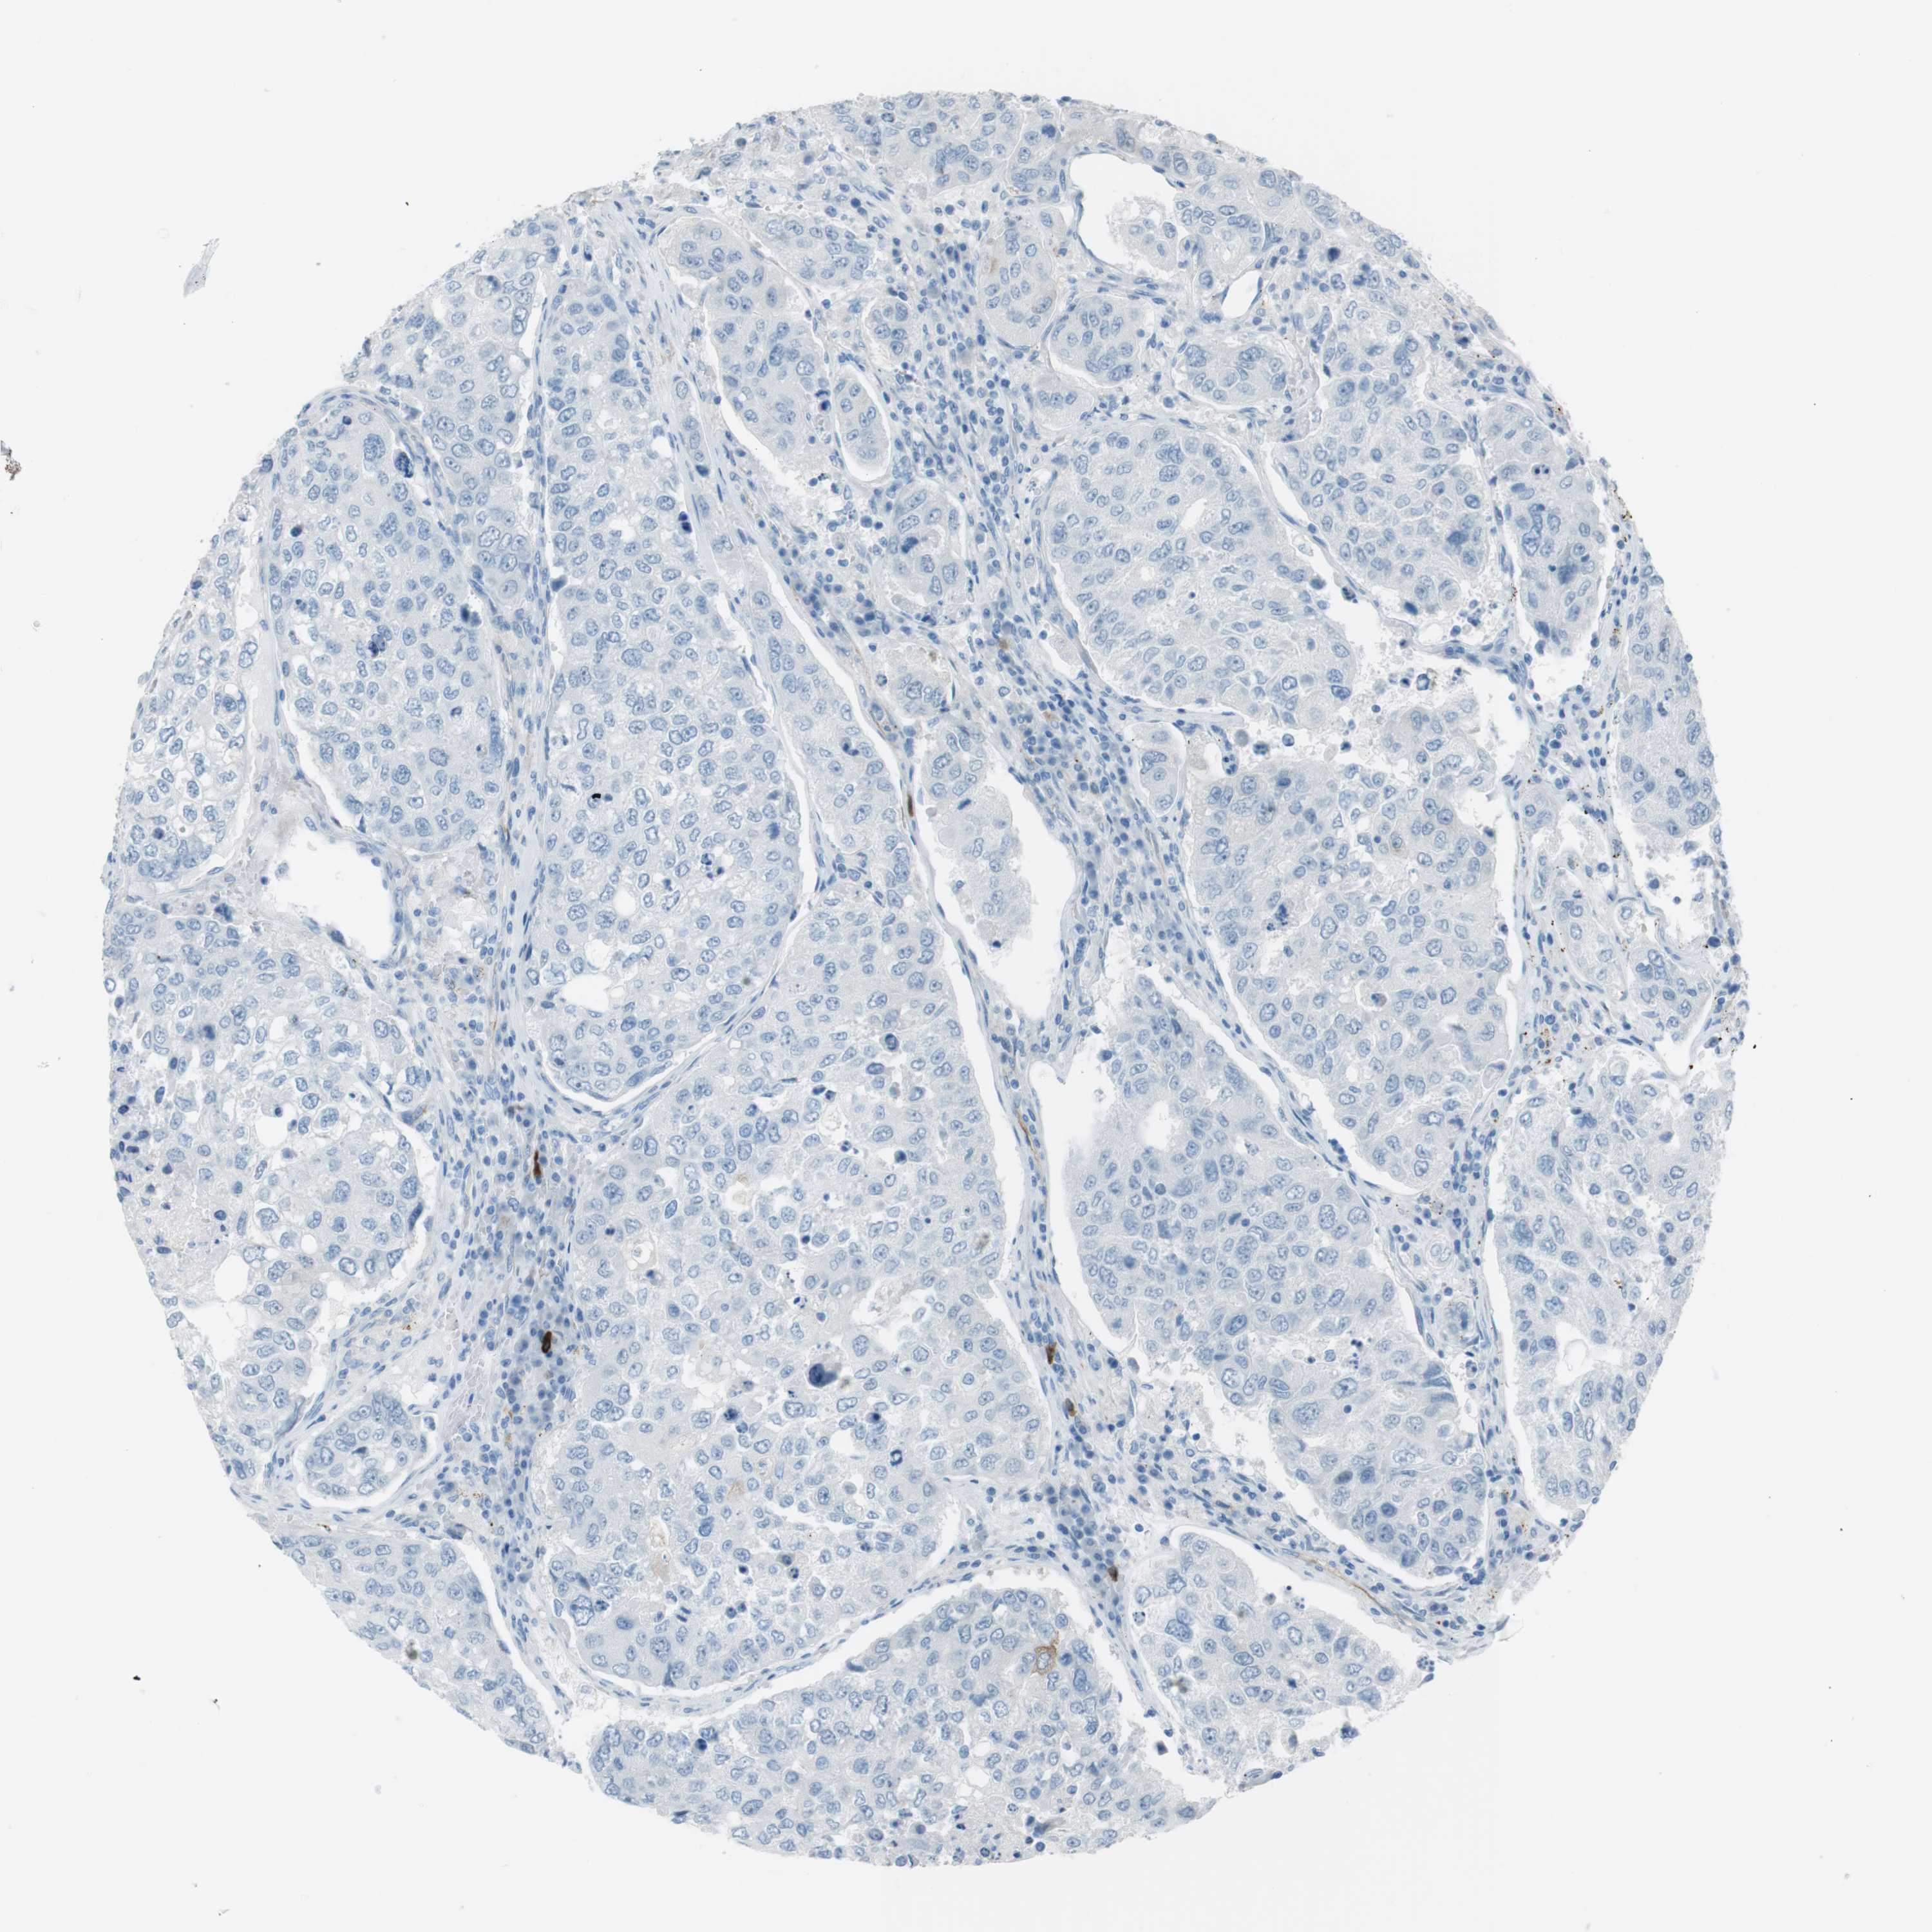

UROTHELIAL CANCER - Protein expressioni

A mouse-over function shows sample information and annotation data. Click on an image to view it in a full screen mode. Samples can be filtered based on level of antibody staining by selecting one or several of the following categories: high, medium, low and not detected. The assay and annotation is described here.

Note that samples used for immunohistochemistry by the Human Protein Atlas do not correspond to samples in the TCGA dataset.

Antibody stainingi

Antibody staining in the annotated cell types in the current human tissue is reported as not detected, low, medium, or high, based on conventional immunohistochemistry profiling in selected tissues. This score is based on the combination of the staining intensity and fraction of stained cells.

Each image is clickable and will lead to virtual microscopy that enables deeper exploration of all samples and also displays staining intensity scores, fraction scores and subcellular localization as well as patient and tissue information for each sample.

Antibody HPA043640

Antibody HPA046280

Antibody CAB015339

Urothelial carcinoma, High grade

Urothelial carcinoma, Low grade